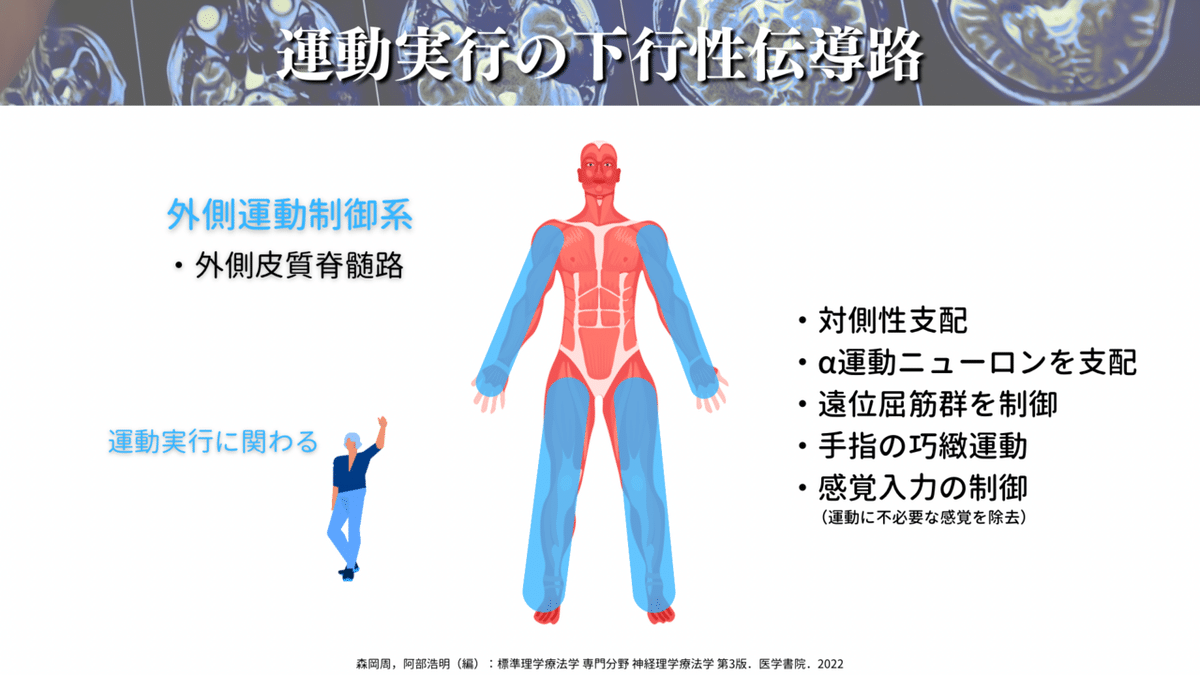

さて、もう少し機能についてお話しをすると、CSTは主に脳と反対側の上下肢を制御していて、特に遠位部の制御を担っています🖐️

CSTは外側皮質脊髄路(LCST)と前皮質脊髄路(ACST)に分かれますが、80〜90%がLCSTですので、CST=LCSTという認識でもOKです👌

LCSTは特に上肢・手指との関連性が強く、LCSTの55%は頸髄レベルに終止すると言われています🖐️

僕たちが行う、手を挙げる動作(バナナをとるなど)や細かな動作(例えばスマホの操作や箸の操作など)はLCSTが大活躍しているわけですね🍌